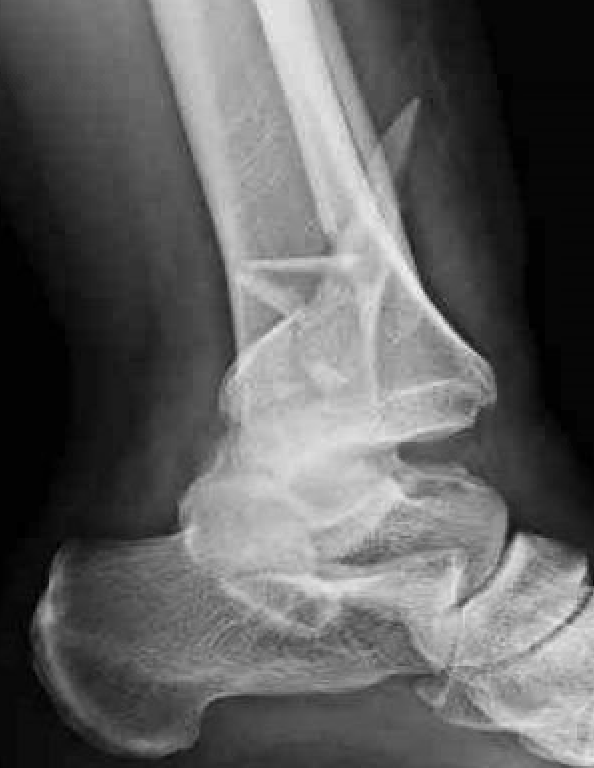

Fibular fracture + posterior malleolus

Postero-lateral approach

| Fibula | Posterior Malleolus | Syndesmosis |

1. Interfragmentary lag screw + neutralisation plate

2. Locking plate |

Buttress plate +/- screws |

Usually stable with fixation of posterior malleolus Screen +/- stabilize |